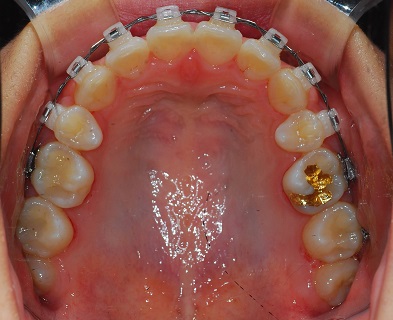

먼저 상악사진입니다

발치공간은 다 매꿔진지 벌써 오래네요

보시면 윗니의 중앙과 아랫니의 중앙이 맞지 않는데 이 중심을 맞추는 것이 이번 치료가 될 것 같아요~